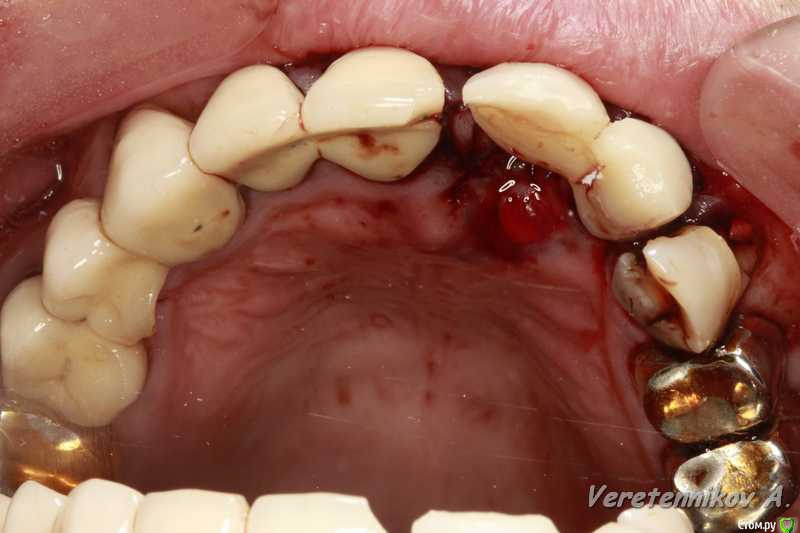

an_ver Опубликовано 26 марта, 2015 Поделиться Опубликовано 26 марта, 2015 (изменено) 11,12..11 трещина корня,вест.часть,12 рыхло все..сгнило.Убрал,кюретаж,11 вест. стенки нет на 2/3.Установил 11-4,2*13;12-3,75*13 мм..все Альфа.Мп3,мембрана эволюшн.11 заглушил,12-временный абатмент,коронка.Шил викрил 4,0. Фсе...пинайте Изменено 26 марта, 2015 пользователем an_ver 7 Ссылка на комментарий

an_ver Опубликовано 27 марта, 2015 Автор Поделиться Опубликовано 27 марта, 2015 Андрей, все вроде ок , смущает два вопроса навскидку. 1) непосредственная нагрузка консолью . Я бы так не рисковал .2) этап планирования. В таких кейсах я предпочитаю все демонтировать - и оценить состояние зубов, и уже после этого планировать удаления / имплантацию. Объясни, почему так поступил? Андрей, все вроде ок , смущает два вопроса навскидку. 1) непосредственная нагрузка консолью . Я бы так не рисковал .2) этап планирования. В таких кейсах я предпочитаю все демонтировать - и оценить состояние зубов, и уже после этого планировать удаления / имплантацию. Объясни, почему так поступил? 1.На 11 вестибулярно нет на 2/3 высоты.Засыпал мр3+мембрана..чет очкуя я на такие грузить((. Предлагаем ему все снять,и если что времянки поставить..отказался на публике часто))) мало ли что))).но ничего швы сниму и это тоже сдерну Ссылка на комментарий

an_ver Опубликовано 28 марта, 2015 Автор Поделиться Опубликовано 28 марта, 2015 В данном случае, если нет Фдм или коронки и надо ушиться, VIP-CT был бы лучше. Имхо!Когда буду времянкой нагружать 11, сальца коллагенового добавлю)) Ссылка на комментарий

an_ver Опубликовано 29 марта, 2015 Автор Поделиться Опубликовано 29 марта, 2015 Понравилось. Смело. Но меня тоже консоль смущает...... Я бы не рискнул ТАК нагружать.вообще консоль на имплантанте это разве норм? Каппу бы ему сделали прозрачную, а там где удалились зубы- пластмасски беленькой. И раскручивайте на снятие соседей- там, видать , тоже все печальноДа тут раскручивать не надо,сам он все понимает.Каппу предлагал.Счас все устаканиться,швы сниму и дальше пойдем Ссылка на комментарий